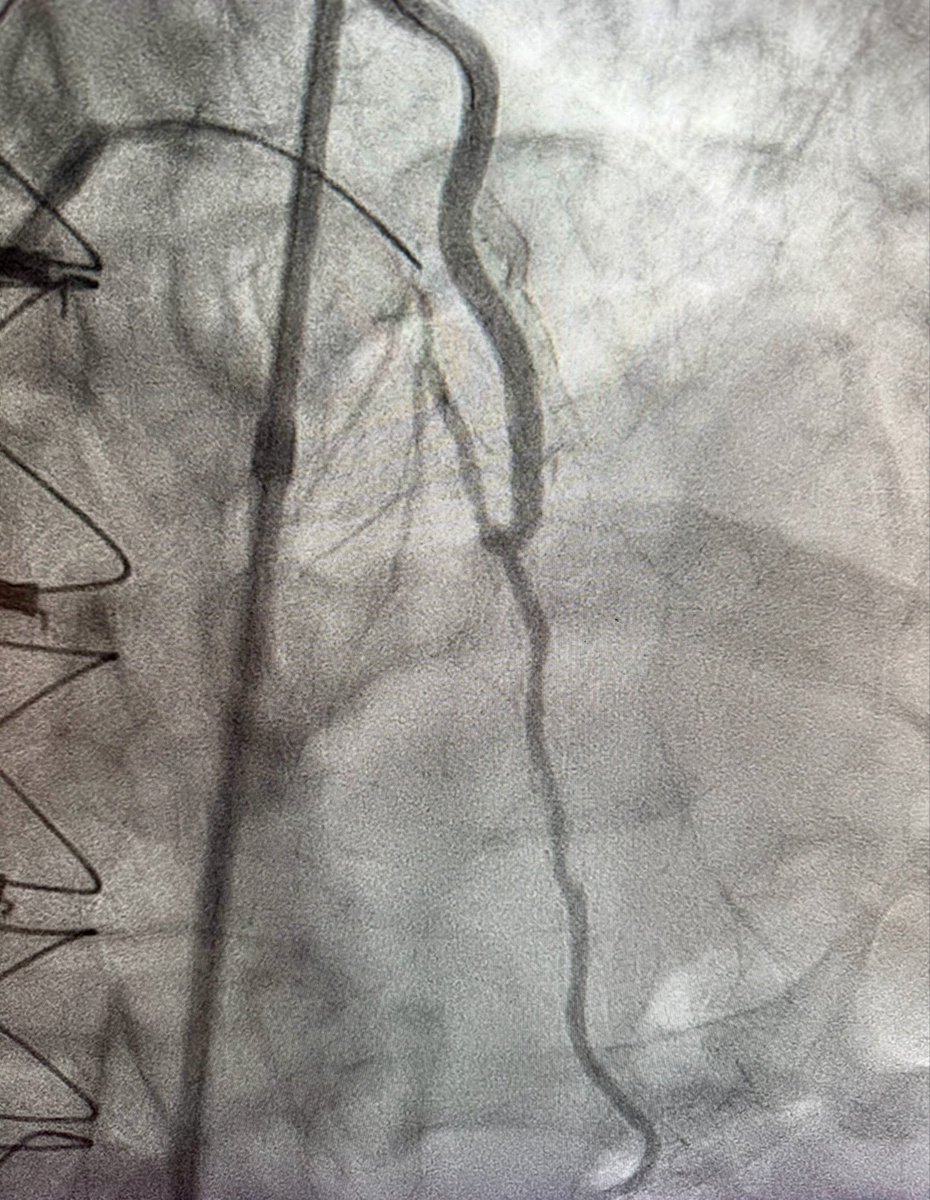

CTO LAD 🔹Dual injection 🔹RCA with wire protection 🔹LAD with microcatheter 🔹Trapping technique to secure the wire 🛑 Always secure the donor first 📍 Microcatheter = Stability + Roadmap ⚠️ Don’t rush the setup, good prep = smoother case 😁 Happier than the patient. #CTO…